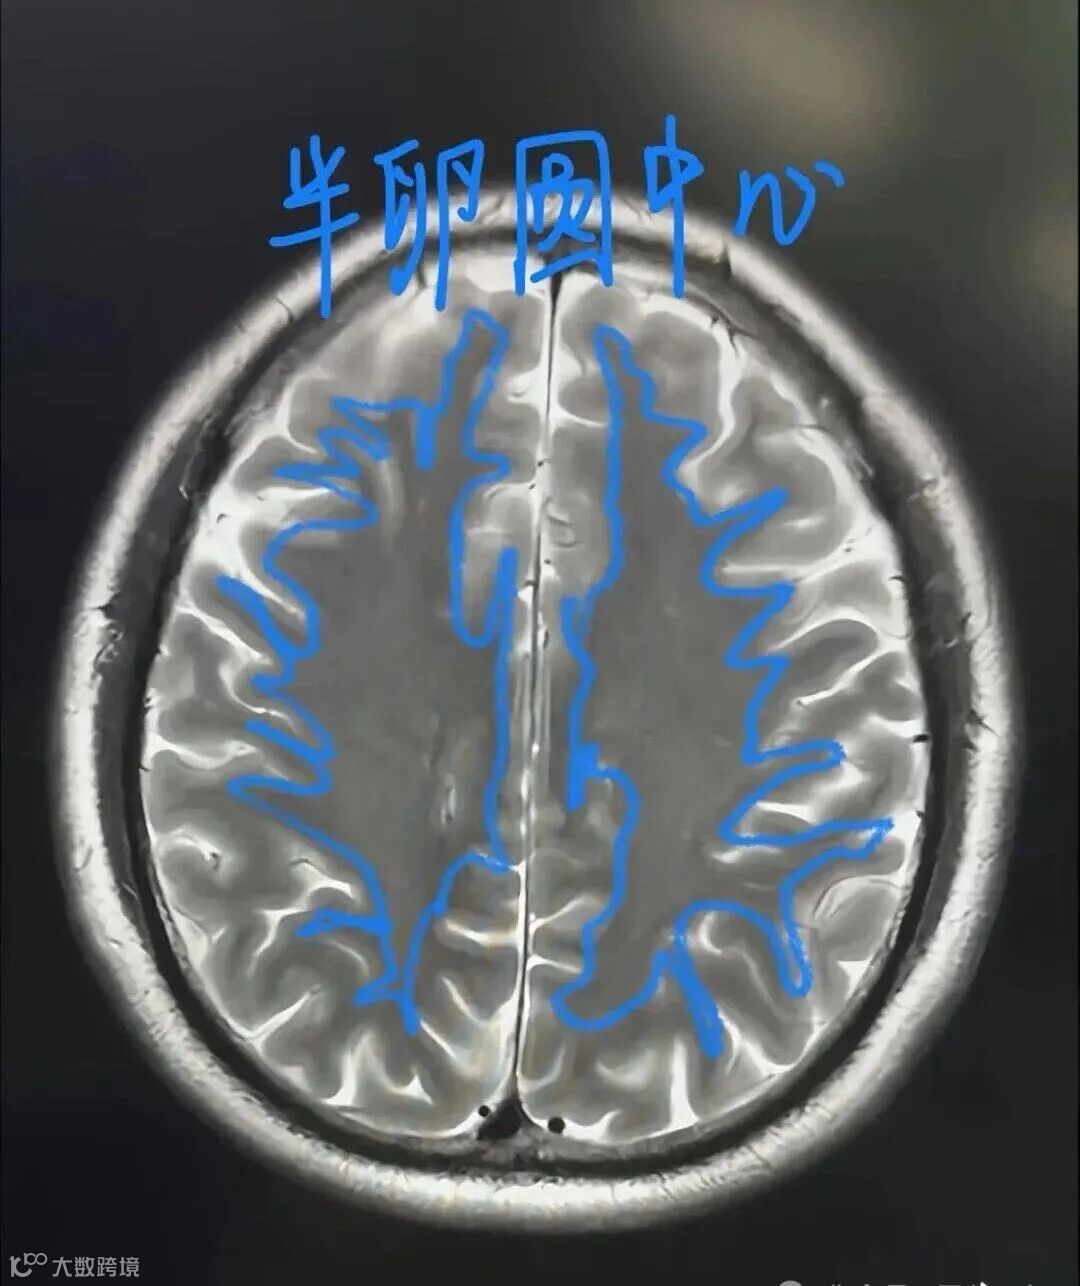

半卵圆中心:指脑室上部的脑白质区域(层面上不出现侧脑室)